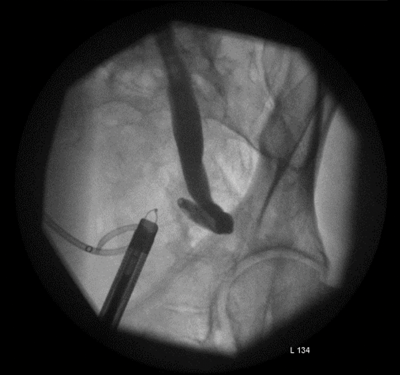

Figure 3.

The lower ureter was tortuous and of the ‘fish-hook’ type. A nephrostogram revealed a stricture at the vesicoureteric junction (VUJ) and incision of the VUJ using a Collins knife failed to demonstrate the lumen (Figure 2 and 3).